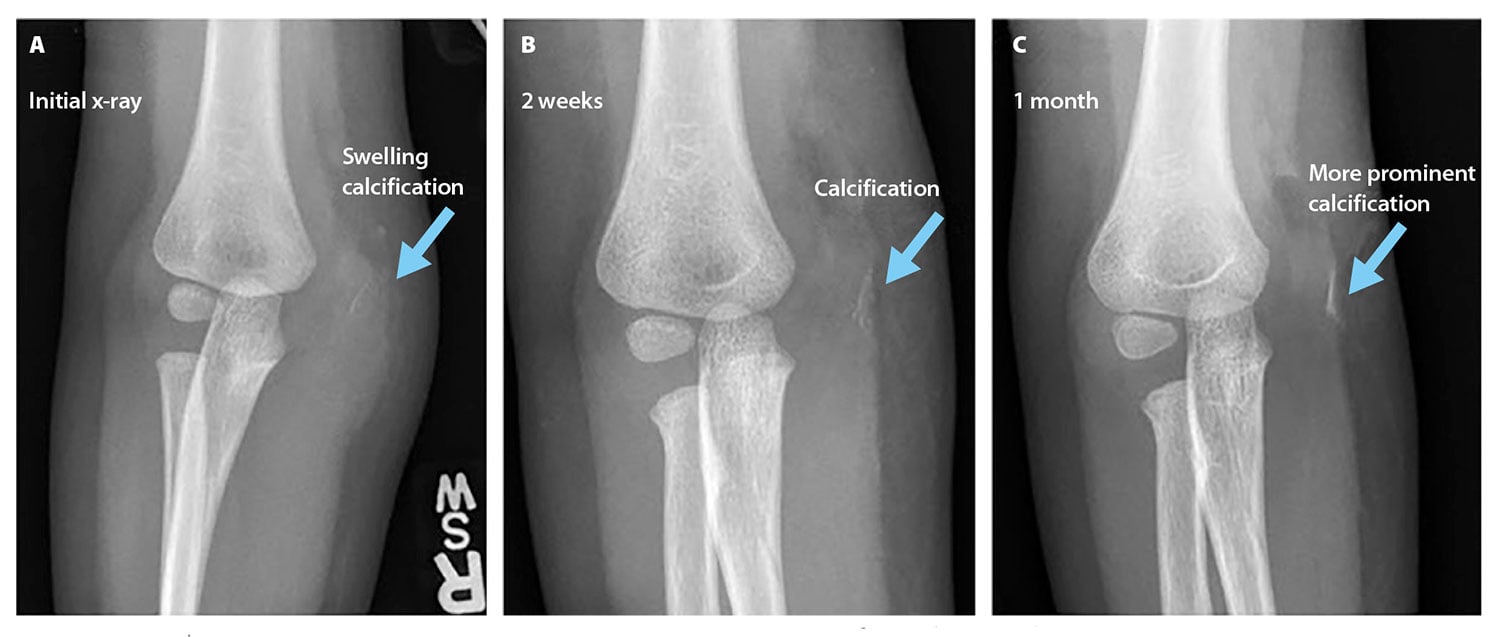

A 2-year-old child presented to the emergency department with right elbow pain after falling off a bench at school. The emergency department physician noted swelling around the medial condyle and decreased range of motion. A radiograph of the injured elbow revealed evidence of soft-tissue swelling but no fracture (see Figure 2). The patient was discharged and instructed to wear a sling for 1 to 2 weeks and to follow up with the orthopedics department.

At a follow-up appointment with the orthopedics department, the patient continued to exhibit pain and swelling in the right elbow, as well as an inability to straighten the elbow and a refusal to use the right arm. A radiograph revealed decreased soft-tissue swelling and a posterior fat pad, not previously observed, that indicated possible joint effusion. The radiograph also revealed a calcification in the area of the swelling (see Figure 2). These findings indicated a possible fracture, and the patient’s right elbow was placed in a cast for 2 weeks.